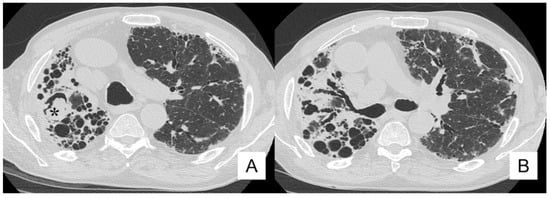

4.5. Pulmonary Infection